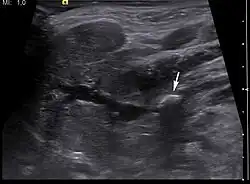

-

Ultrasound image of sialolithiasis -

Stone resulting in inflammation and dilation of the duct[9]